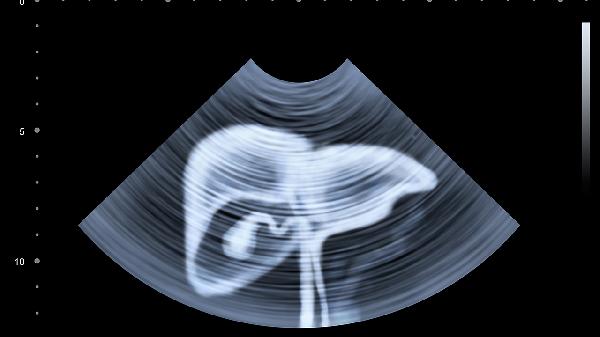

维护肝脏健康需保持规律作息,避免熬夜和过度劳累。饮食上控制高脂高糖食物摄入,适量补充优质蛋白和维生素。建议定期进行肝功能检查,出现持续乏力、黄疸等症状应及时就医。日常可饮用菊花茶、枸杞茶等具有保肝作用的饮品,但避免盲目服用护肝保健品。